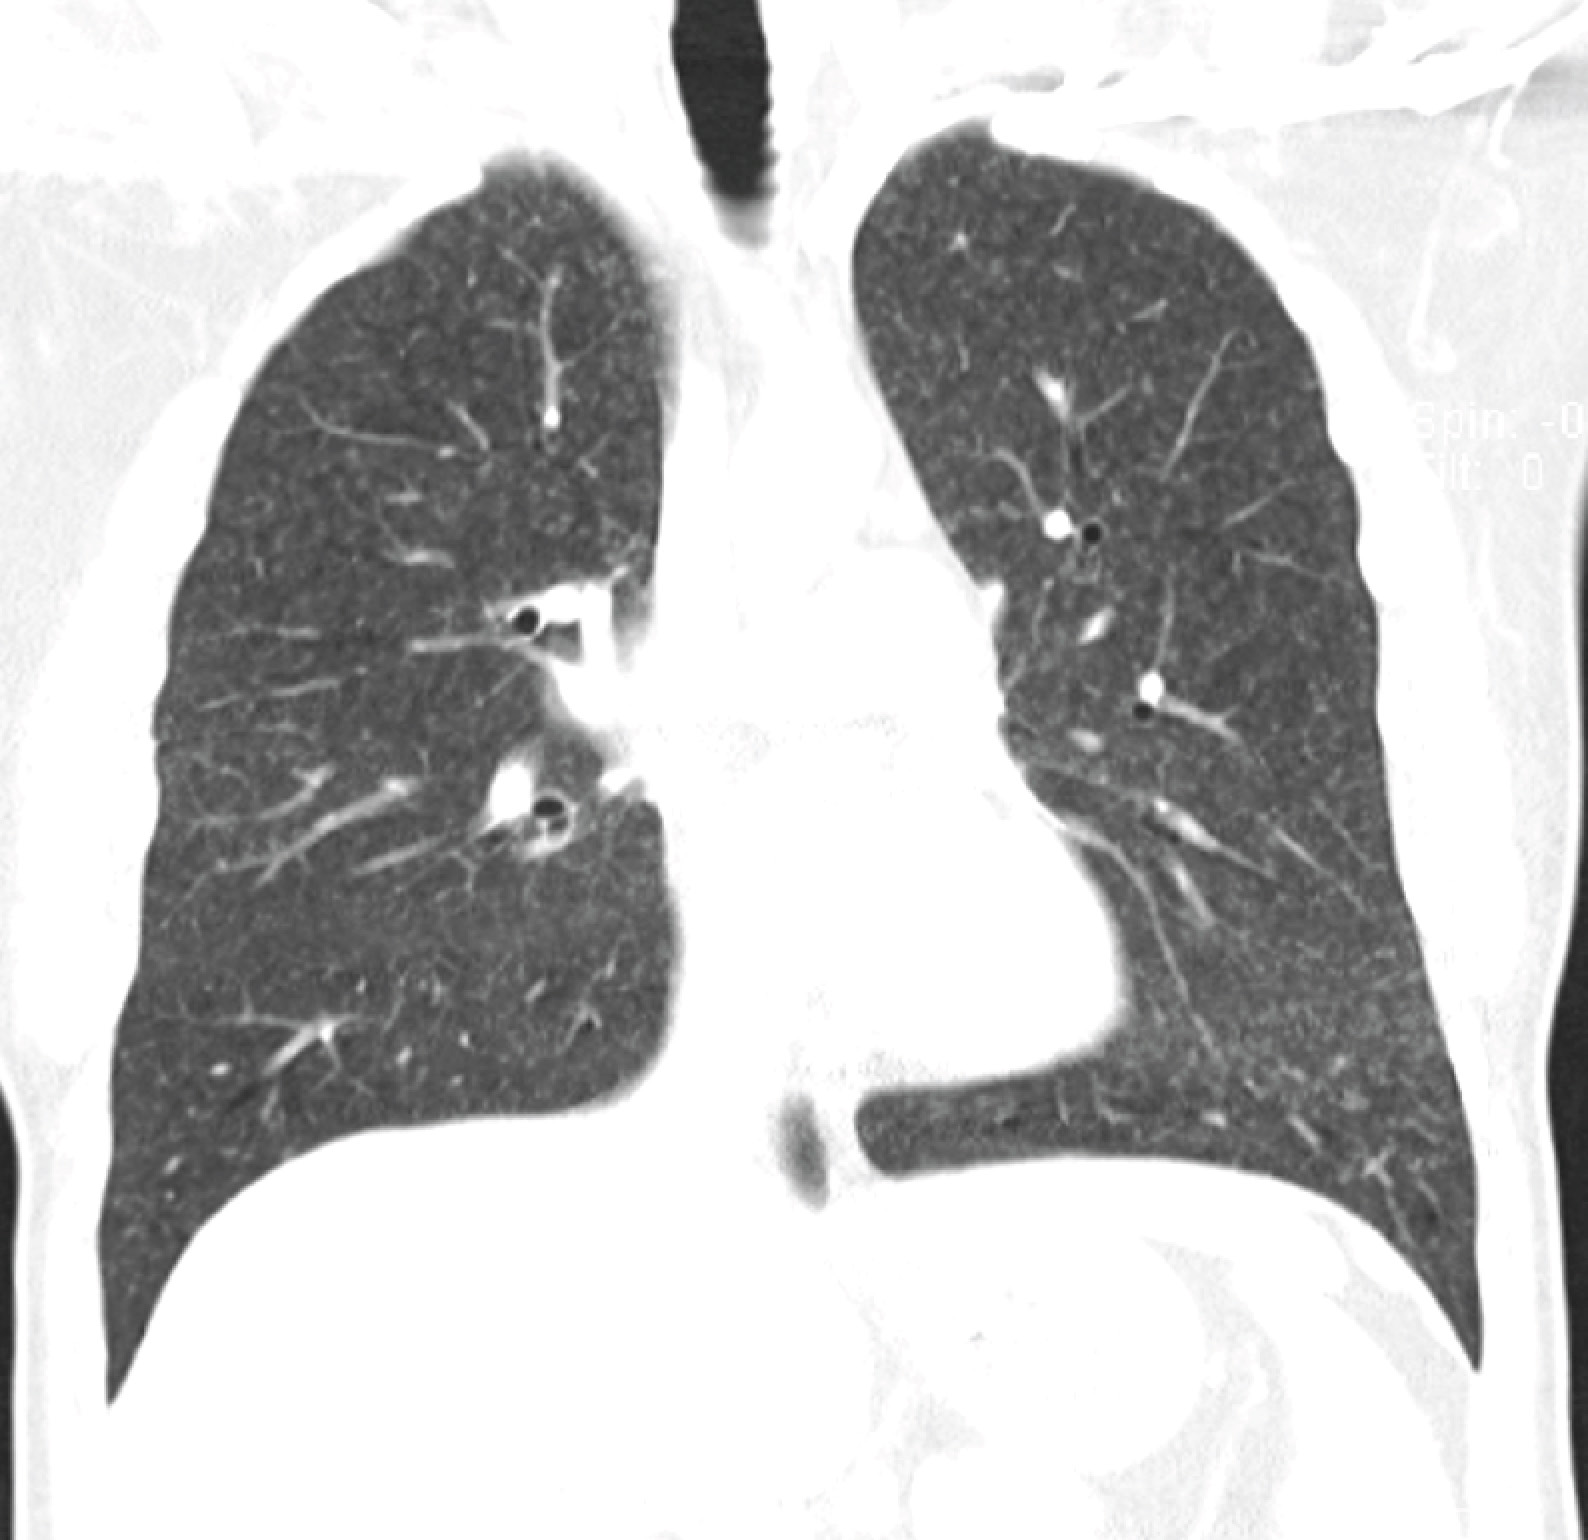

Clinical examination was unremarkable except for a drop in SpO2 to 92% after a brisk walk around the hospital room. The chest X-ray showed faint miliary shadows in both lung fields (the CXR image is provided below, but unfortunately the resolution is insufficient to permit visualisation of the abnormalities), which was confirmed on CT thorax.

The major non-infectious differential is methotrexate pneumonitis. The best review on this topic (in my opinion) was written 15 years ago – a large case series and literature review published in the European Respiratory Journal. The symptoms and clinical presentation are consistent, and nodular infiltrates alone are seen in 4.1% of cases. It is also interesting to note that granulomas are a common histological finding.